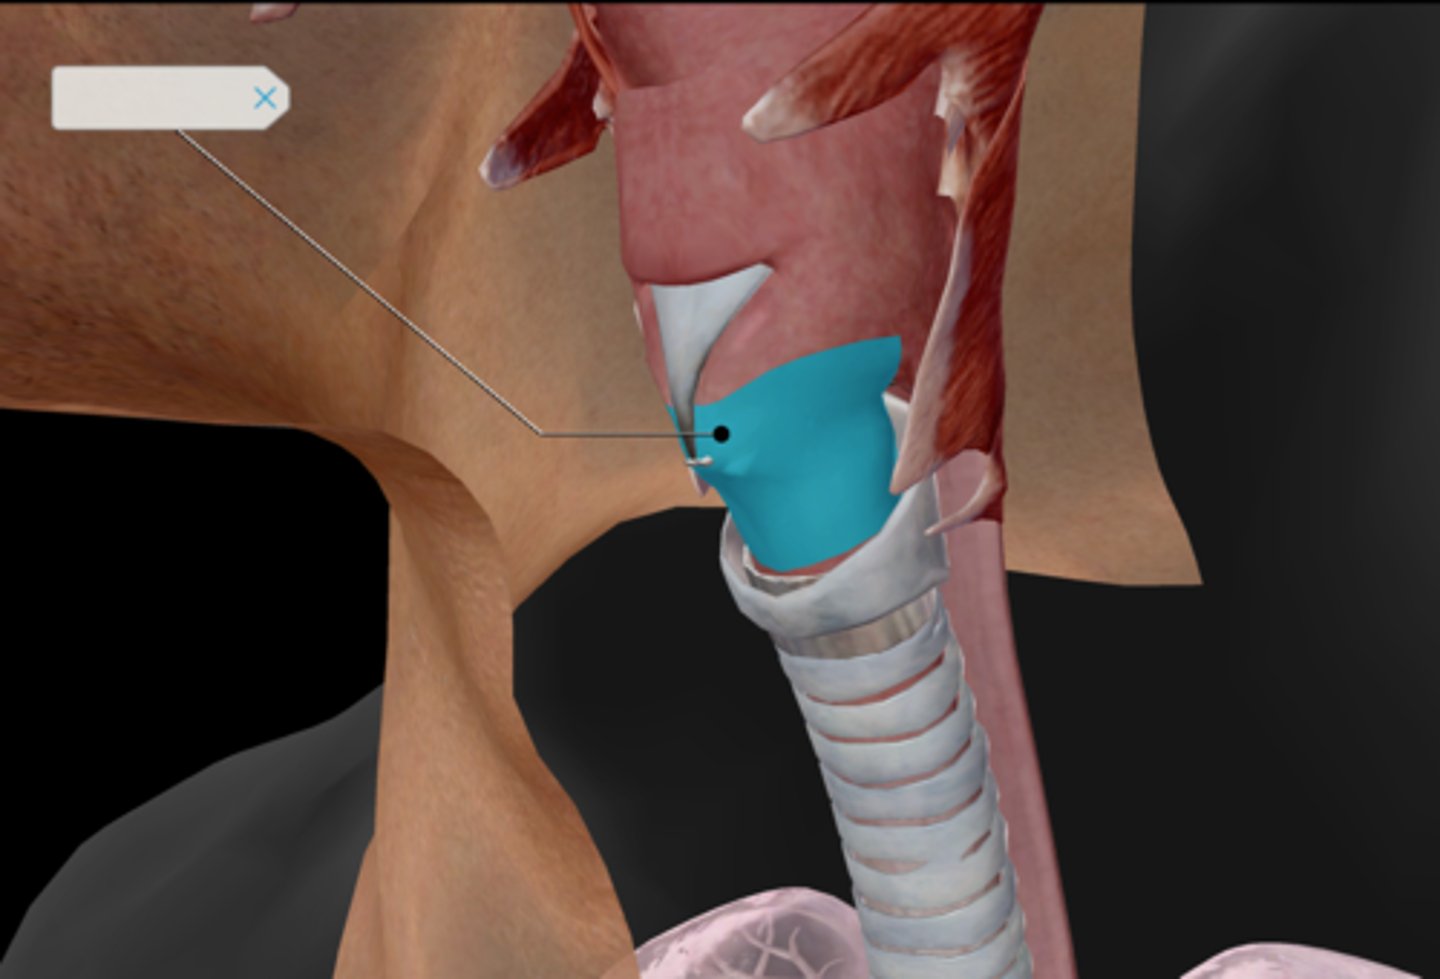

Larynx

Epiglottis

Thyroid cartilage

Cricoid cartilage

Trachea

Tracheal cartilaginous rings